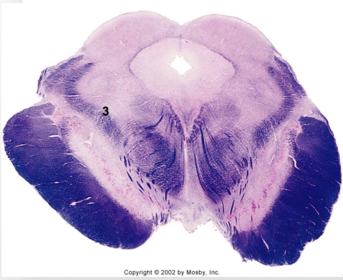

| Medullary pyramids | |

| Hypoglossal nucleus | |

| Hypoglossal nerve | |

| Dorsal motor nucleus of X | |

| Nucleus ambiguus | |

| Solitary tract | |

| Solitary nucleus | |

| ALS | |

| Medial lemniscus | |

| Medial longitudinal fasciculus | |

| Anterior spinocerebellar tract | |

| CN IX | |

| Inferior cerebellar peduncle | |

| Inferior olivary complex | |

| Dorsal cochlear nucleus | |

| Inferior vestibular nucleus | |

| Medial vestibular nucleus | |

| Spinal nucleus of V | |

| Spinal tract of V | |